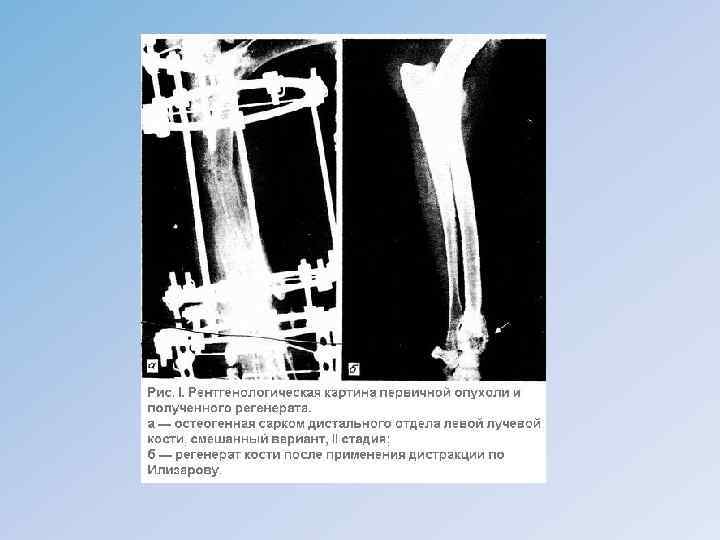

• • Рентгенологически различают следующие разновидности: 1) остеолитическая; 2) смешанная; 3) остеобластическая: а) центральный вариант; б) периферический вариант. Наиболее патогномоническими признаками являются своеобразные остеофиты, возникающие на границе наружного дефекта компактного слоя кости и внекостного компонента опухоли, они имеют вид характерного козырька или треугольной шпоры ( «козырек» Кодмана). Другой симптом – спикулы – тонкие игольчатые обызвествления, расположенные перпендикулярно к длинной оси кости. • Лечение комплексное, включающее лучевую и химиотерапию, хирургическое вмешательство. Оперативное пособие чаще всего заключается в ампутации, в последнее время выполняются сегментарные резекции с последующей костной пластикой или эндопротезированием. После проведенного комплексного лечения пятилетняя выживаемость составляет от 35, 5 до 60 %.

ХОНДРОСАРКОМА проксимального отдела бедренной кости.